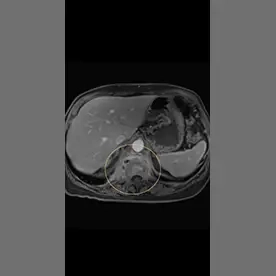

In der angefertigten MRT des LWS und des Abdomens zeigt sich eine kräftige T2w-Signalanhebung in den Wirbelkörpern BWK 12 und LWK 1 mit Irregularitäten der Abschlussplatten (Bild 1). Die angrenzende Psoasmuskulatur zeigt sich auch signalalteriert, betont auf der rechten Seite (Bild 2). Bei der Kontrastmittel-Unterstützer-Untersuchung zeigt sich ein kräftiges Enhancement in den Wirbelkörpern und der angrenzenden Muskulatur (Bild 3). Besonders auf der rechten Seite zeigen sich zudem auch abszessartige Formationen (Bild 4).

Der Befund ist vereinbar mit einer Spondylodiszitis von BWK 12/LWK 1 mit Absenkung in den Musculus psoas beidseits, rechtsbetont, differentialdiagnostisch ist hier an eine Tuberkulose als Ursache zu denken.